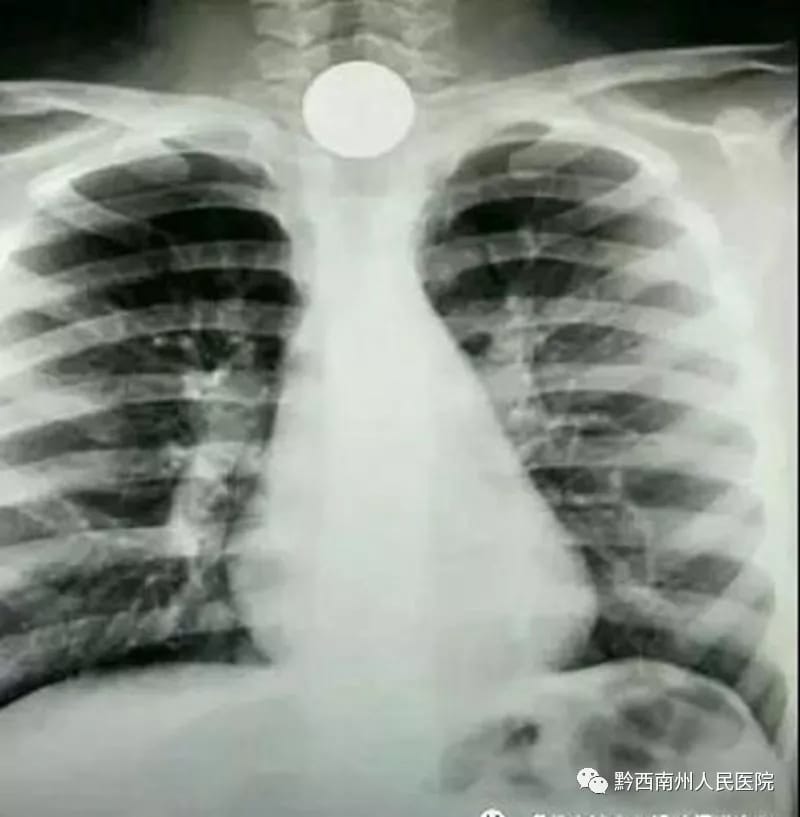

近几年来,内镜科镜下取异物的手术也越来越多,大部分都是小孩子。孩子们对这个世界充满着幻想,对一切事物都比较好奇,把硬币、纽扣、小玩具放到嘴巴里,一不小心就吃进肚子里,还把自己吓得哇哇大哭,而家属也极度焦虑、自责。因为异物留在孩子们的身体内危害很大,不知道会突发什么情况,所以我们配台的护士更要精、准、快,从而降低手术的风险,手术时护士又充当着“家长”的角色,一边哄着他们,一边配合着医生进行异物取出。而每当异物被取出,家属一副轻松的表情,不停的道谢,心底虽累,却也累并快乐着。